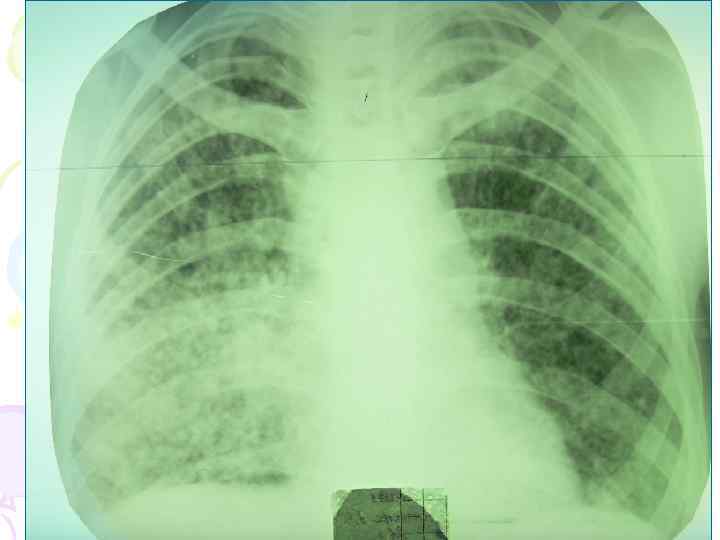

Рентгенологическая картина • множественные крупные / до 10 мм/ однотипные очаги преимущественно в верхних и средних отделах легких • Очаги округлой формы, малой и средней интенсивности, контуры нечеткие, часто расположены в виде цепочки вдоль продольных сосудов • Сливаясь, очаги образуют фокусы затемнения с участками просветления (распад) • При распаде в нескольких отдельных очагах формируются кольцевидные тени – штампованные каверны • При лимфогенной диссеминации очаговые тени с одной стороны, в средних и нижних отделах на фоне лимфангита, в корне кальцинаты

Рентгенологическая картина • Наблюдается полиморфная картина: очаги различной величины, формы и интенситвности, свежие и старые на фоне фиброзных изменений, больше в верхних отделах • Тенденции к слиянию очагов нет • Нарушается симметричность поражения • Могут наблюдаться как тонко- так и толстостенные каверны • Верхушки - интерстициальный фиброз, уменьшение объема, плевральные наложения, в нижних отделах - викарная эмфизема. С-м плакучей ивы. • Тень сердца сужена, имеет срединное положение (капельное сердце) • Фиброз и эмфизема обуславливают деформацию бронхиального дерева, что способствует развитию бронхоэктазов

Дифференциальная диагностика милиарного и диссеминированного туберкулеза Проводится с многочисленными легочными диссеминациями /до 20 нозологических групп и более 100 нозологических единиц и синдромов/. Наиболее важные из них: • • • мелкоочаговая двусторонняя пневмония канцероматоз саркоидоз легких пневмокониозы, в частности, силикоз неспецифический пневмосклероз застойные изменения в легких при сердечной недостаточности, особенно, при сочетании их с гипостатической пневмонией • легочные изменения при коллагенозах: СКВ, узелковый периартерит, идиопатический фиброзирующий альвеолит / синдром Хаммена - Рича/, синдром Гудпасчера и др.